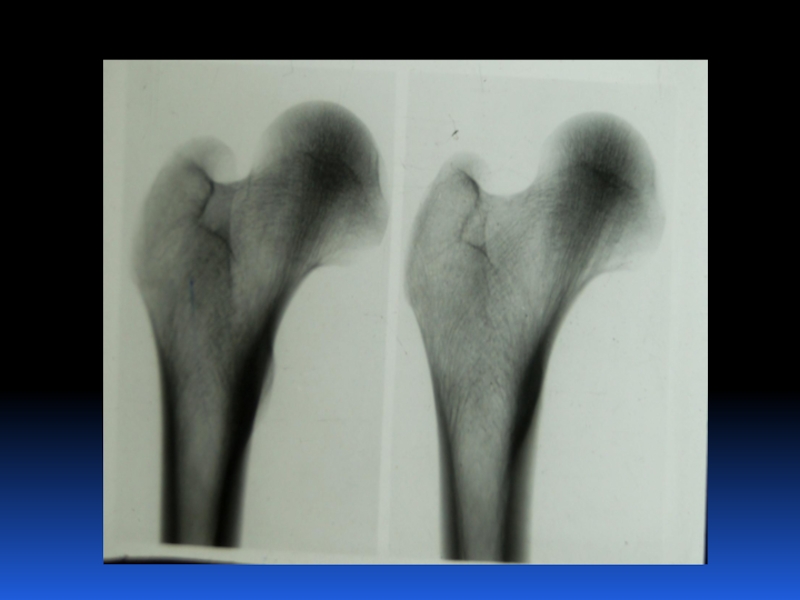

Остеопороз – это системное заболевание скелета, характеризующееся снижением костной массы и нарушением микроархитектоники костной ткани, с последующим увеличением хрупкости костей, со склонностью к патологическим переломам.

Слайд 2 Остеопороз – это системное заболевание скелета, характеризующееся снижением костной

массы и нарушением микроархитектоники костной ткани, с последующим увеличением хрупкости

костей, со склонностью к патологическим переломам.